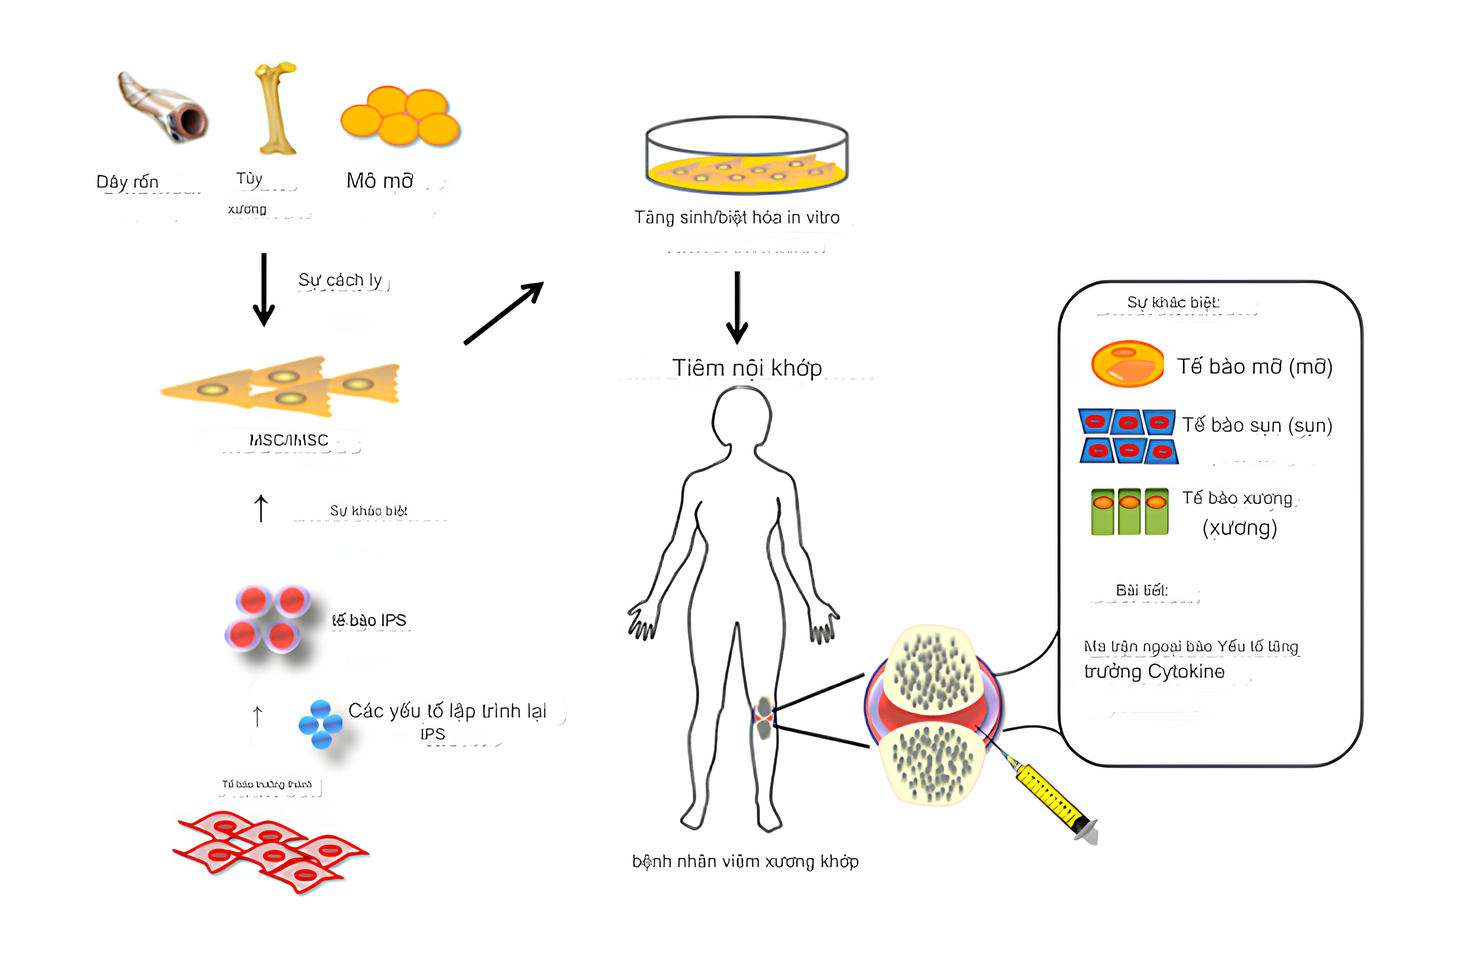

Cho đến nay, phương pháp điện trị liệu đã được ứng dụng để nghiên cứu phản ứng của nhiều loại tế bào như tế bào gốc trung mô, tế bào xương và sụn, tế bào thần kinh và tế bào tim. Và các thí nghiệm trong ống nghiệm đã chỉ ra rằng điện trường ảnh hưởng đến các hành vi quan trọng của tế bào như bám dính, tăng sinh, biệt hóa, di cư theo hướng cũng như phân chia. [17]

Khoa học đã chứng minh rằng liệu pháp kích thích điện không chỉ thúc đẩy sản xuất các chất hóa học liên quan đến quá trình phục hồi tổn thương sụn khớp, mà còn điều chỉnh sự tăng sinh/ phân hóa của MSC. [19]

MSC (tế bào gốc trung mô) là chất đóng vai trò quan trọng trong việc hình thành và phục hồi mô sụn. Do đó, các cơ chế tăng sinh/ phân hóa của MSC do điện trường tác động đã được nghiên cứu sâu rộng. [20]

Báo cáo đánh giá về liệu pháp Tế bào gốc trung mô giúp điều trị thoái hóa khớp (đăng trên tạp chí Am J Transl Res năm 2021) có đề cập đến 3 nhóm MSC được chứng minh là đem lại tác dụng hiệu quả cho việc trị liệu chứng đau nhức & viêm xương khớp, cụ thể là:

- Tế bào gốc trung mô từ tủy xương (BM-MSC) [21]

- Tế bào gốc trung mô từ mô mỡ (AD-MSC) [22]

- Tế bào gốc trung mô từ dây rốn (UC -MSC) [23]

Các tế bào gốc trung mô có hiệu quả trong việc điều trị viêm xương khớp